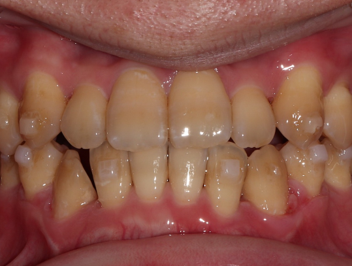

Chen chúc

Chen chúc là tình trạng có sự chênh lệch giữa kích thước răng và không gian có sẵn để sắp xếp răng trên cung răng.

Thông tin bệnh nhân:

Tuổi: 17

Giới tính: nữ

Lựa chọn điều trị Invisalign: Invisalign Comprehensive

Tổng thời gian điều trị:

29 tháng